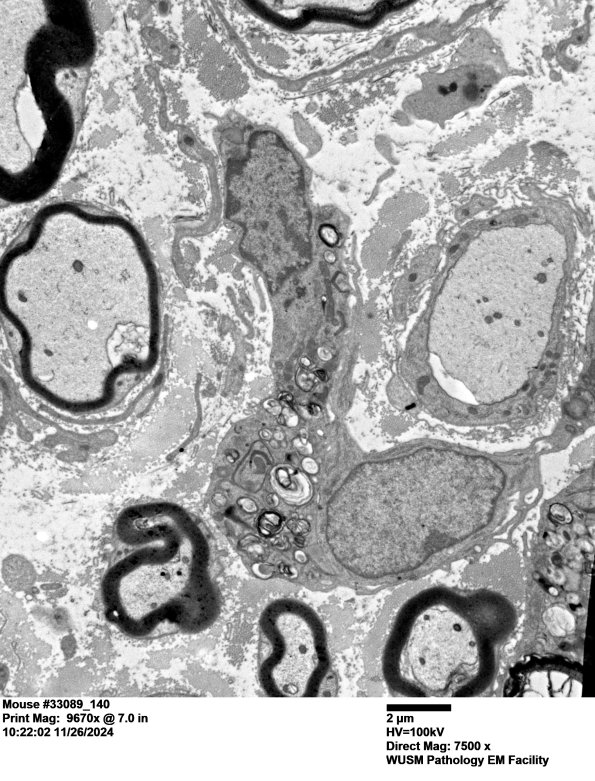

Washington University Experience | PERIPHERAL NEUROPATHY | 6 AXONAL DEMYELINATION (BASIC PROCESS) | 2A4 Mouse #33089 (Case 2) 140a.jpg

A macrophage with cytoplasmic myelin debris within the endoneurium flanked by a remyelinating axon and a naked demyelinated axon. (electron micrograph)